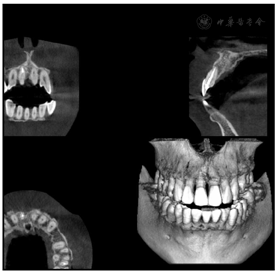

11牙冠完整,扣(-),Ⅰ度松动,唇侧牙龈约牙根中部位置膨隆呈半球型,唇侧牙周袋溢脓,唇侧近中及中央位点PD> 10 mm,余位点PD 2~3 mm。X线根尖片示:11近中牙槽骨环绕牙根牙周病样角型吸收达根尖,远中牙槽骨未见明显异常,见图1。CBCT示:11唇侧近中牙槽骨环绕牙根缺损自冠方达根尖,根中段疑似根折影像,见图2。

患者初次就诊临床检查11唇侧近中可及深窄牙周袋,x线片11近中牙槽骨角型吸收达根尖就考虑该牙是否存在根裂,因为大多数根纵折的一侧均会有深及根尖部的狭窄牙周袋[3]。x线片根纵裂的特点是有沿牙长轴的牙槽骨吸收,呈现沿根尖至根侧的"J"型骨吸收表现、日晕状或角形吸收[1]。但x线片及CBCT均未见明确根折根裂影像,且开髓后根管长度测量仪能正常侧量工作长度,故而首诊未行手术探查,仅行根管治疗封氢氧化钙及龈下刮治。患者封药2周、4周复查11深窄牙周袋无改善,仍溢脓,根据以往经验,如牙根无缺陷,行标准的根管治疗封药2-4周基本牙龈症状均会消除,故而此时我们决定翻瓣手术探查。翻瓣刮除大量肉芽后于11根中部见隐裂,明确了诊断。